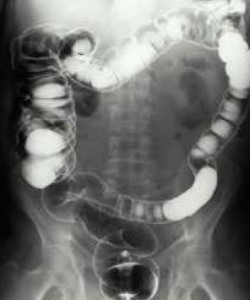

Burada, kalın bağırsağın renklendirilmiş röntgen filmini görüyorsunuz.